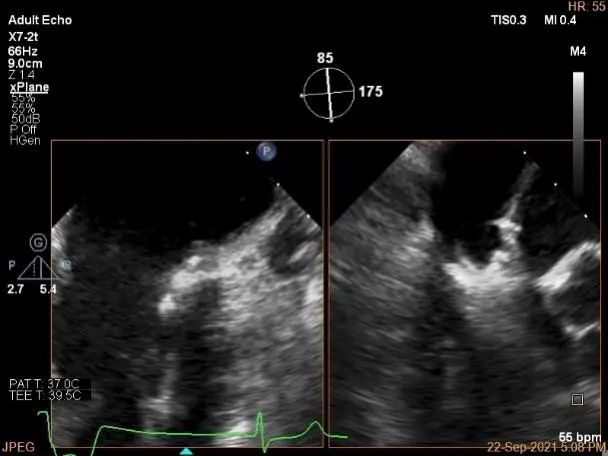

3D:P1区脱垂并腱索断裂,部分AC受累,Width:11.4mm

房间隔穿刺点选择

穿刺高度:4.08cm

根据Expand研究,有1/3以上的MR患者为复杂MR。本例患者为P1接近前交界区的腱索断裂,在MR评估方面,应该注意评估二尖瓣返流的具体受累区域、返流方向,血流束宽度,反流量分级及受累区域的最大宽度,以此作为制定手术策略的主要参考依据。脱垂宽度及血流束累及范围、有效返流口面积、平均跨瓣压差及瓣叶长度可以有效帮助术前判断夹子类型、大小及植入数量,对受累区域的定位还可以帮助确定房间隔穿刺的高度及范围。另外,对肺静脉血流频谱形态的采集,还可以辅助评估返流分级。该患者术前二尖瓣返流定量参数及肺静脉血流频谱均提示患者存在重度4级的返流。脱垂区域位于1区靠前交界处,提示穿刺高度可以在正常低限(4-5),该例患者术中穿刺高度4.08cm,基本符合手术方案要求。